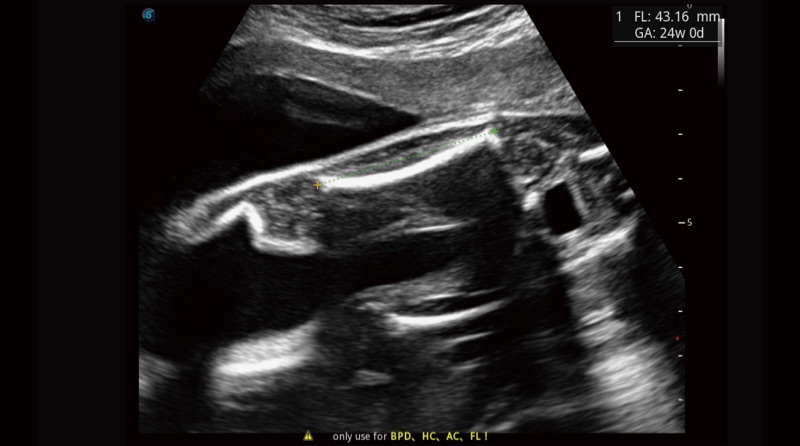

Basierend auf einem verlässlichen Deep-Learning-Algorithmus für Big Data ist S-Fetus eine brillante Komplettlösung für automatische Standard-Ebenen-Erfassung und Messung. Mit nur einem Klick werden gängige fetale Biometrie-Ergebnisse mit hoher Intelligenz, Genauigkeit und Effizienz erzielt, um einen beispiellosen Bedienungskomfort zu gewährleisten.

Dank der Unterstützung von Auto OB wird eine schnelle und hoch effiziente fetale Biometrie erreicht. Gleichzeitig kann diese auf Deep Learning basierende Methode zu konsistenteren Ergebnissen führen und die Variabilität, die vom Anwender abhängig ist, effektiv reduzieren.